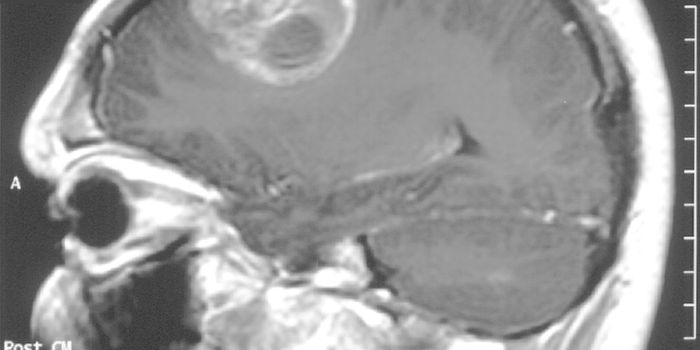

OCT 15, 2016Clinical & Molecular DXGlioblastomas are notorious for being inoperable. That’s why when scientists developed a laser method to “co ...